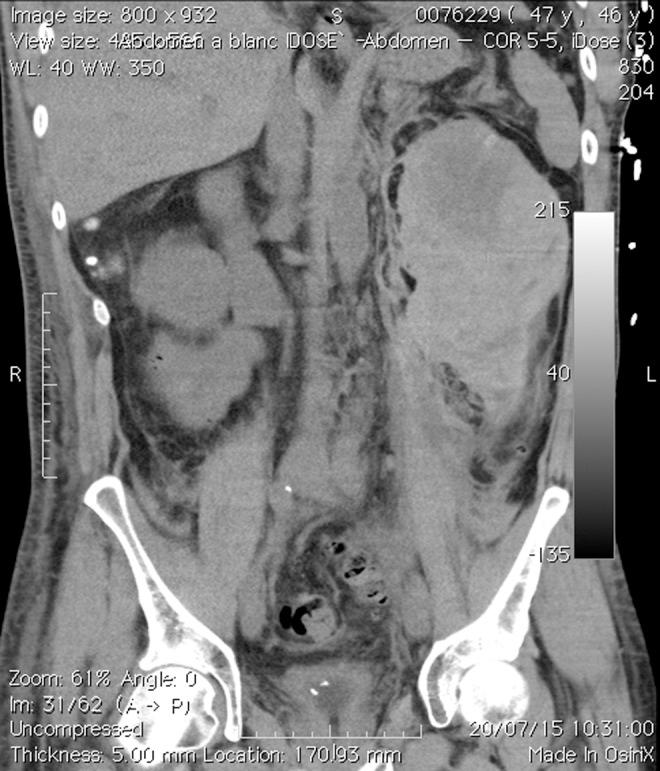

Extracorporeal shockwave lithotripsy (SWL) is a commonly used technique for treating urinary calculi. Although noninvasive, highly effective, and widely accepted, SWL is not without complications. Next to fragmenting the calculi, the surrounding tissue is damaged, which can result in renal hematoma, a well-described complication. In most cases, the collateral tissue damage is mild and resolves with conservative treatment. However, rarely, severe complications may arise. Here we present a case of a 46-year-old male who developed a massive hematoma, both subcapsular and retroperitoneal, after a third consecutive SWL session, resulting in hypovolemic shock. Different probable causes are proposed, of which one cause, the length of the interval between SWL sessions, is not yet studied properly. Probably, short intervals keep the damaged tissue from healing sufficiently, as proposed in our case. Possibly, life-threatening situations can be avoided if more evidence-based guidelines are available.

体外冲击波碎石术(SWL)是治疗尿路结石常用的技术。虽然SWL是非侵入性的、高效的且被广泛接受,但并非没有并发症。除了将结石击碎外,周围组织也会受到损伤,这可能导致肾血肿,这是一种广为人知的并发症。在大多数情况下,附带的组织损伤较轻,通过保守治疗即可解决。然而,很少会出现严重并发症。在此,我们报告一例46岁男性病例,该患者在连续第三次接受SWL治疗后,出现了巨大的包膜下和腹膜后血肿,导致低血容量性休克。我们提出了不同的可能原因,其中一个原因,即SWL治疗疗程之间的间隔时间,尚未得到充分研究。正如我们病例中所提出的,可能短间隔会使受损组织无法充分愈合。如果有更多基于证据的指南,可能可以避免危及生命的情况。